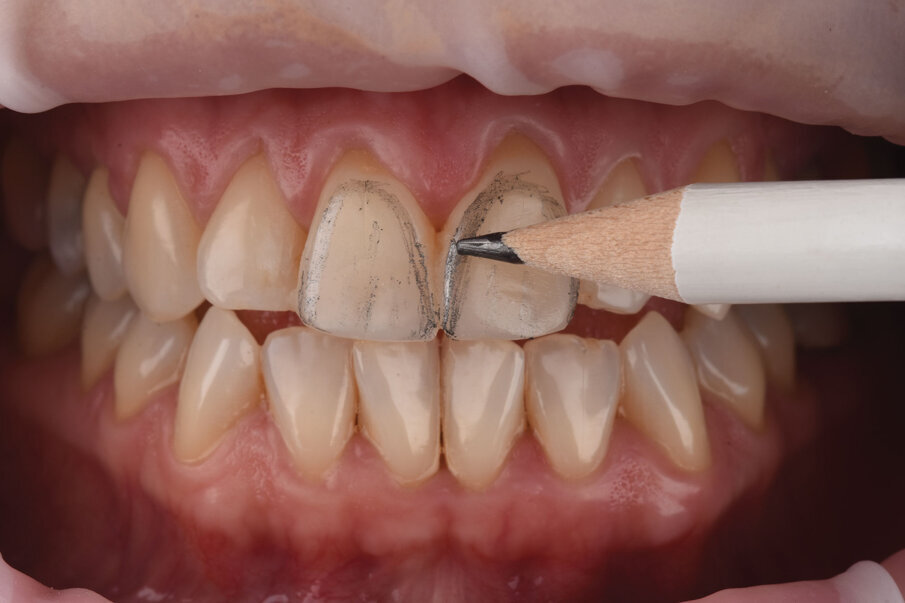

Sl. 4a: Polarizovana fotografija uz tzv. button tehniku (4b) i izrada individualnog ključa boja sa kompozitnim sistemom izbora adekvatan su način pravilnog odabira boje.

Sl. 4b: Polarizovana fotografija uz tzv. button tehniku (4b) i izrada individualnog ključa boja sa kompozitnim sistemom izbora adekvatan su način pravilnog odabira boje.